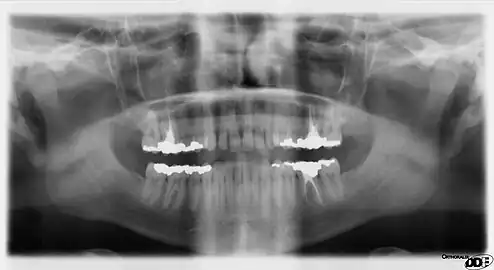

- A panoramic radiograph reveals the mandible, including the heads and necks of the mandibular condyles, the coronoid processes of the mandible, as well as the nasal antrum and the maxillary sinuses.